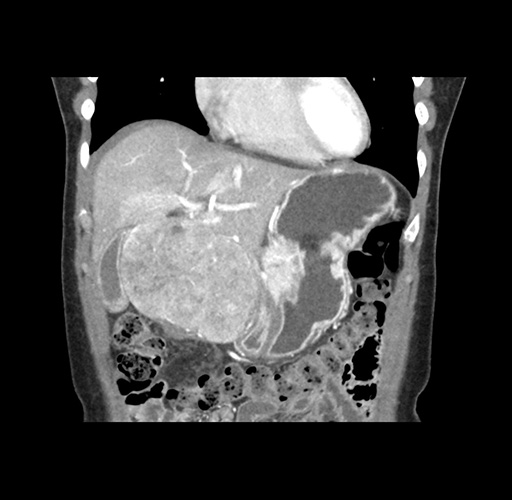

Imaging Analysis

Look through the patient's CT scan to identify any areas of concern for the necessary procedure.

Based on your CT findings, which issue(s) would give reason for "planned slowing down moment(s)" in this case?